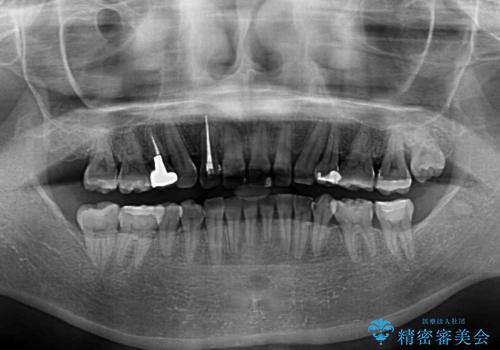

咬合力が非常に強く、スペースがなかなか閉じなかったことと、上下の正中が著しくずれてきてしまったため、下顎左側小臼歯を途中抜歯することとなりました。

歯の動きが鈍く、矯正治療だけで4年以上の期間を要することとなりました。

矯正治療後は、気になっていた銀歯を全てセラミックとし、きれいな口元に仕上げることができました。